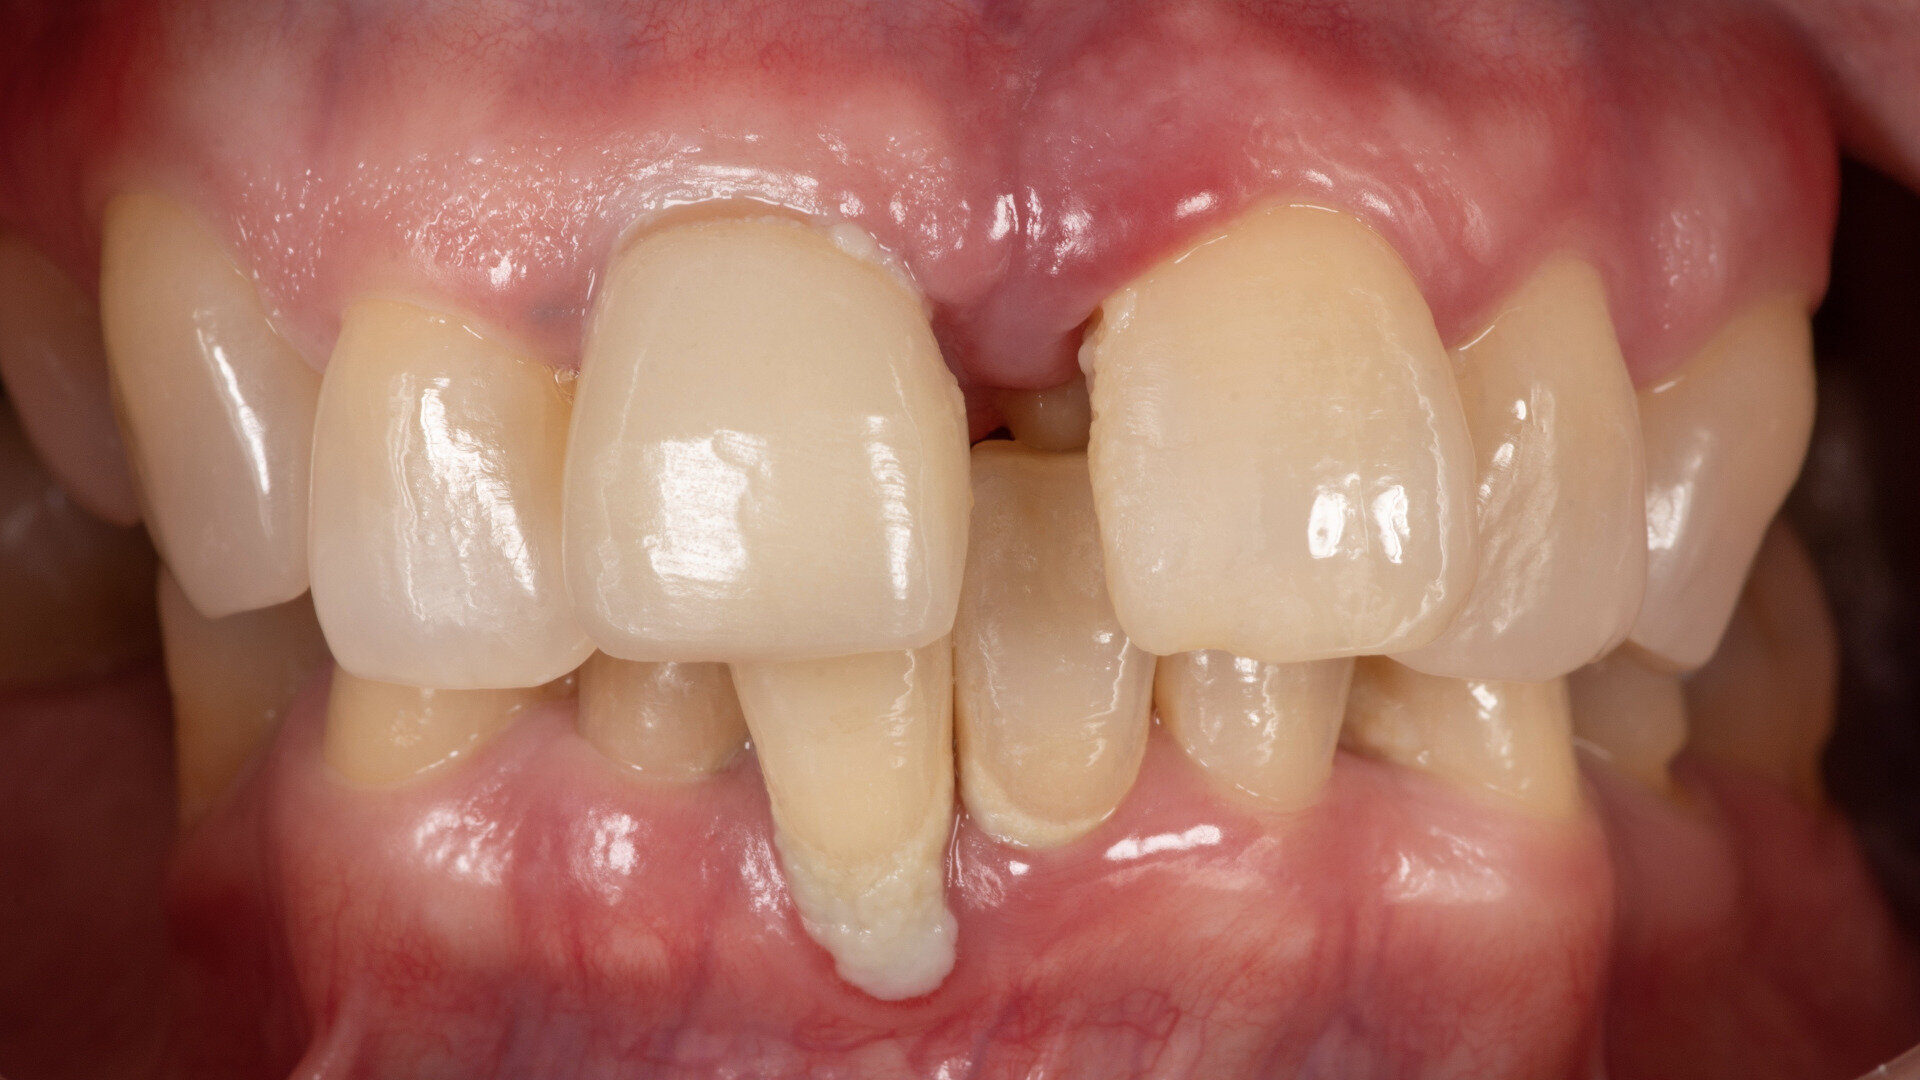

A 57-year-old female patient who was systemically healthy and a non-smoker and had no relevant medical history came to our clinic stating that she was unable to eat without pain and had absolutely no confidence or pride in her smile or overall appearance. She had also noticed flaring and progressive spacing of her anterior teeth and complained of food impaction. She desired a full-mouth fixed rehabilitation and wanted to improve the position of her teeth to regain the confidence to smile.

No abnormalities were found during the extra-oral examination. The patient presented with a low smile line. The intra-oral examination revealed terminal dentition due to generalised periodontal disease. The patient presented with severe resorption of the posterior maxilla bilaterally (Fig. 1). The radiographic examination showed generalised alveolar bone resorption with vertical bone defects (Fig. 2).